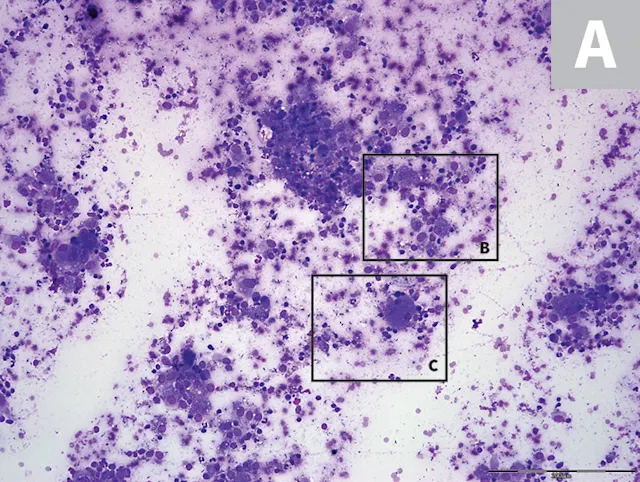

Rectal scraping was highly cellular with numerous inflammatory cells, including predominantly macrophages and fewer neutrophils, lymphocytes, and plasma cells. Some macrophages and neutrophils contained varying numbers of 3- to 5-μm yeast with a basophilic nucleus and a small clear perinuclear halo. Abundant bacteria, frequent RBCs, and a background of amorphous cellular and fecal debris were also present (Figures 3). There was no evidence of fungal pulmonary nodules on thoracic radiographs.